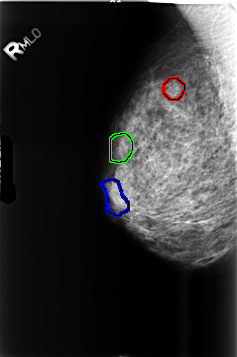

B_3460_1.RIGHT_MLO

FILE: B_3460_1.RIGHT_MLO.OVERLAY

TOTAL_ABNORMALITIES 3

ABNORMALITY 1

LESION_TYPE MASS SHAPE LOBULATED MARGINS CIRCUMSCRIBED

ASSESSMENT 3

SUBTLETY 3

PATHOLOGY BENIGN

ABNORMALITY 2

ABNORMALITY 3